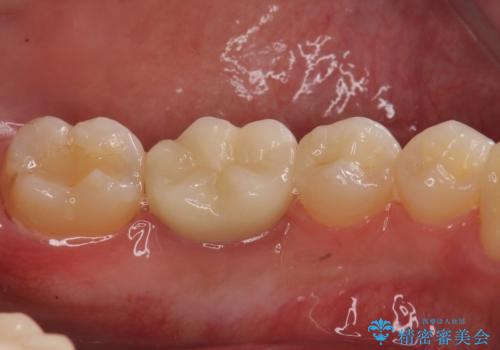

銀歯のやり替え セラミックで白い歯に

虫歯治療に加え、奥の銀歯も同時にやり替えました。

精度の良いクラウンにやりかえることは今後の虫歯リスクを減らすことにつながります。